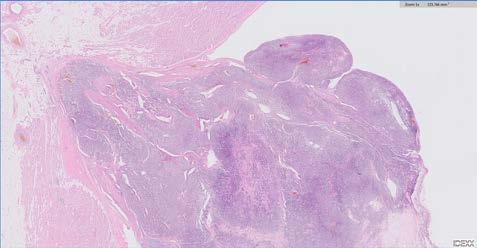

Figura 2. Linfoma epiteliotrópico en unión mucocutánea. Infiltración linfoide neoplásica en dermis superficial (flecha negra) y mostrando comportamiento epiteliotrópico (flecha blanca) (tinción hematoxilinaeosina, 30 x).

El estudio histopatológico por escisión de la trufa mostró hiperplasia epidérmica y una intensa infiltración dérmica superficial multifocal a difusa, conformada por células linfoides de tamaño medio, con anisocariosis moderada, escaso citoplasma y mitosis aisladas, observándose infiltración focal en la unión dermoepidérmica (epiteliotropismo) (Fig. 2). El diagnóstico presuntivo fue de linfoma epiteliotrópico. El estudio inmunohistoquímico evidenció una población linfoide CD3+, CD20-, fenotipo correspondiente a una población de linfocitos T, que confirmó el diagnóstico de linfoma epiteliotropo cutáneo asociado a fenotipo T (Fig. 3).

Figura 3. Linfoma epiteliotrópico en unión mucocutánea. Células neoplásicas de imagen anterior (Fig. 2) mostrando tinción positiva a CD3, infiltrando dermis superficial (flecha negra) y mostrando comportamiento epiteliotrópico (puntas de flecha negras) (tinción de linfocitos T mediante técnica inmunohistoquímica con anticuerpo anti-CD3 y contraste con hematoxilina, 30 x).